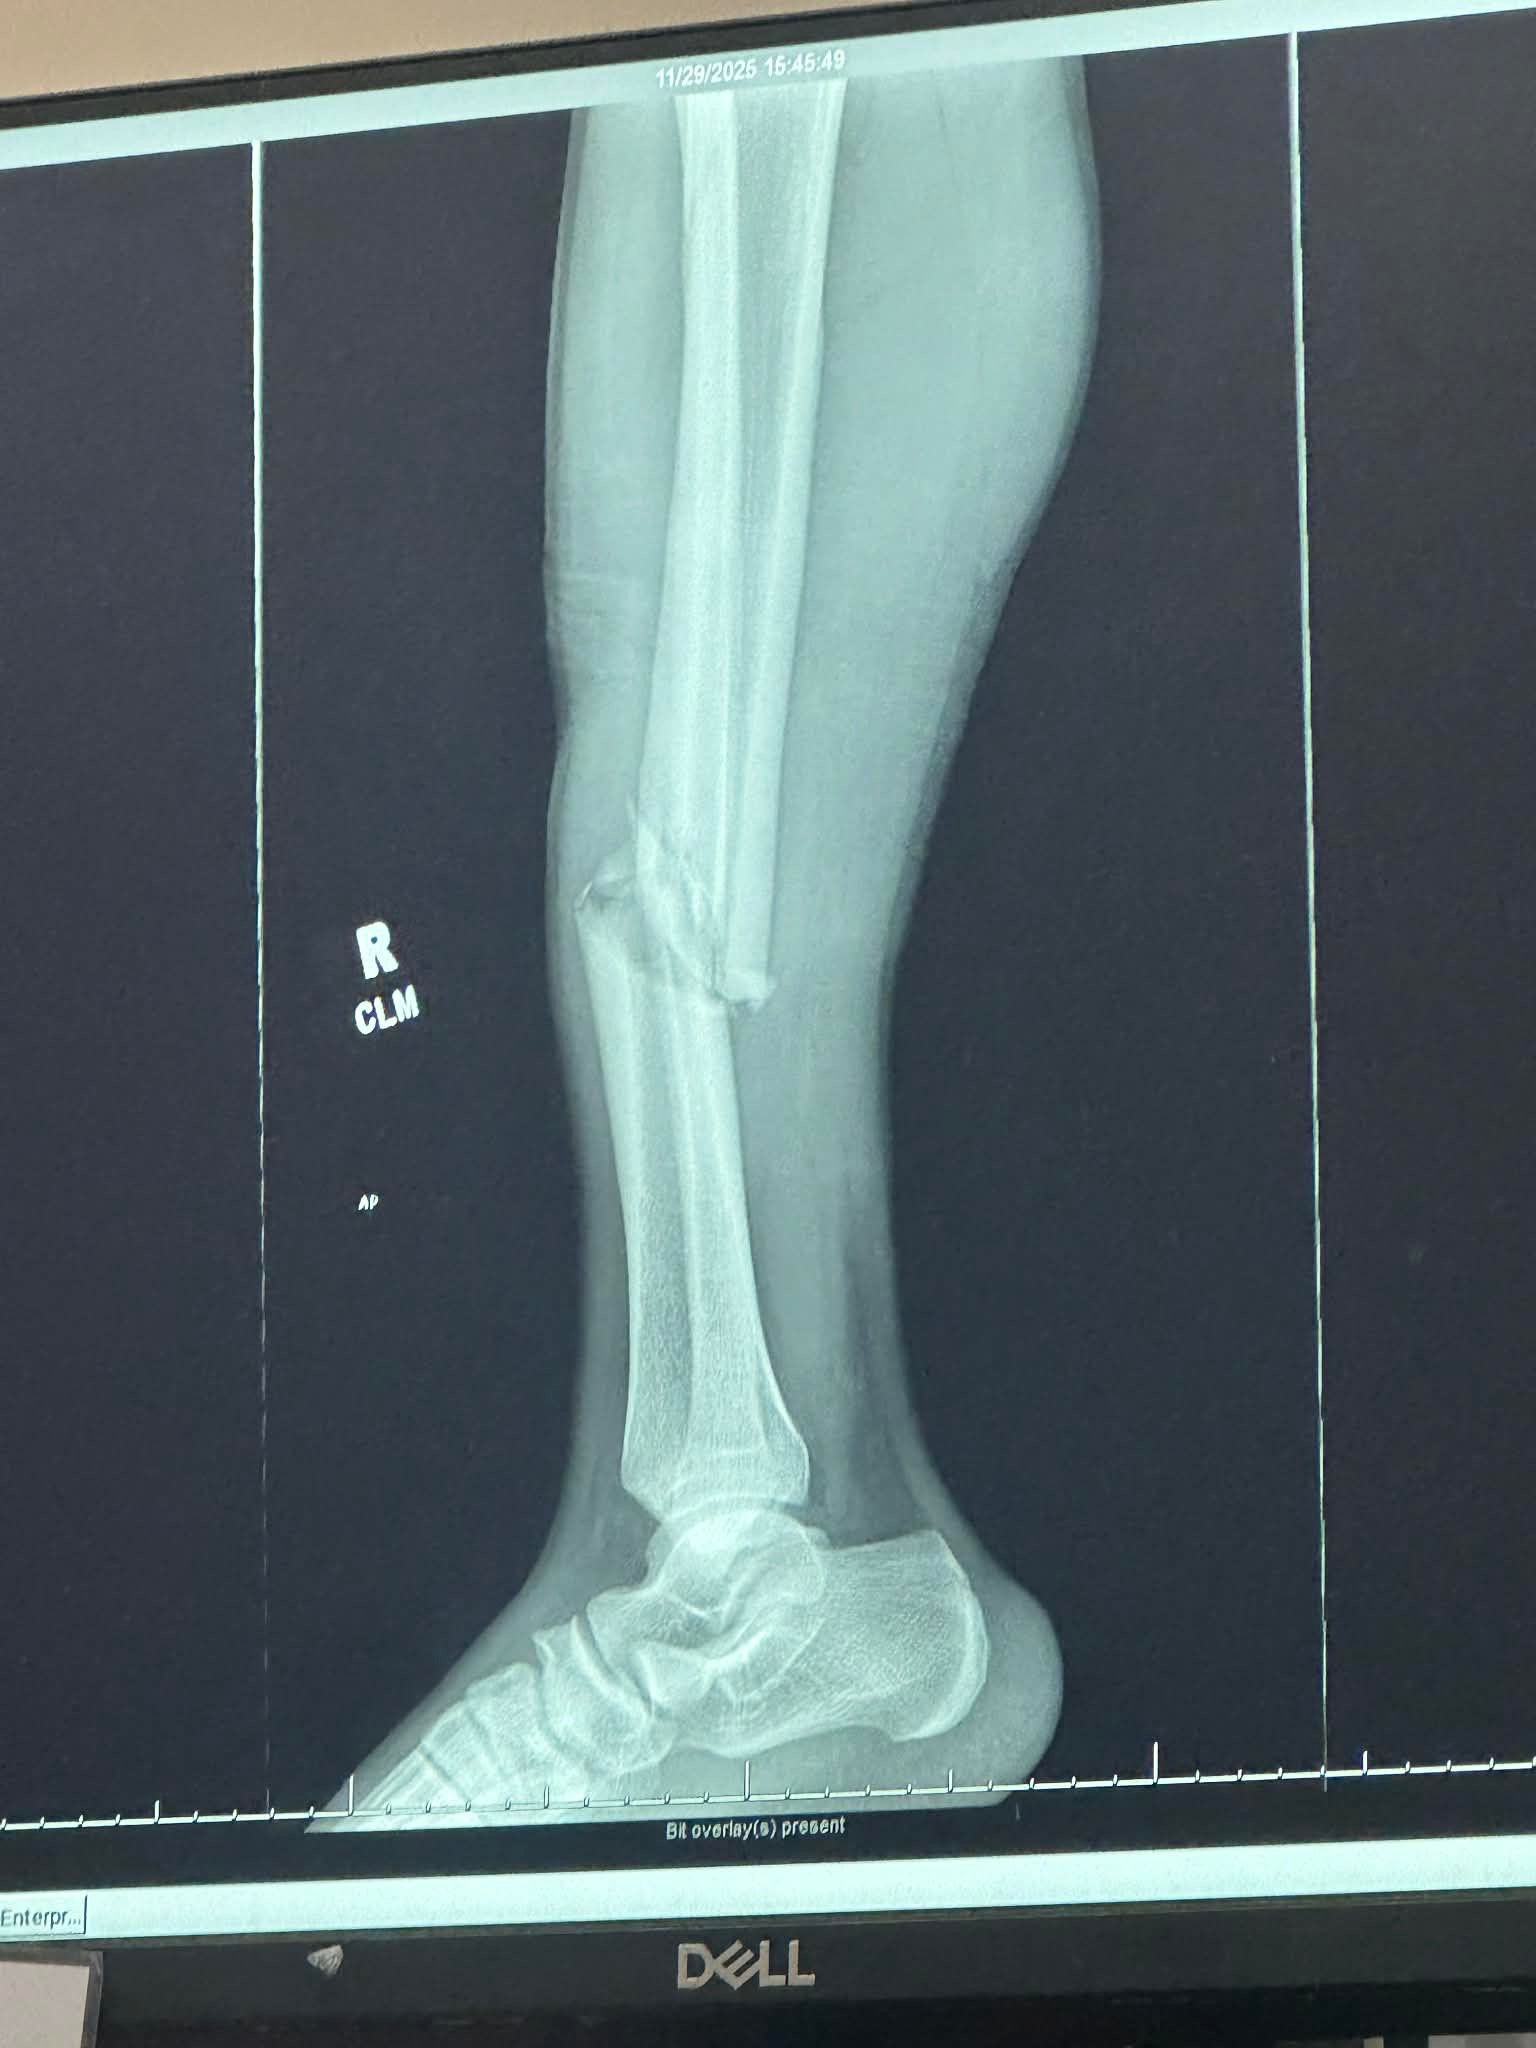

On November 29th, my dear friend, Tyler Ward, was riding his bike to the firehouse he volunteers at to respond to a call. In his travels, he collided with a minivan, and his leg was pinned under the tire of the van. Tyler was transported to Lehigh Valley Hazleton and then transferred to Geisinger Wyoming Valley, where he had to get surgery. He has multiple broken bones and also had to get a rod inserted into his leg.